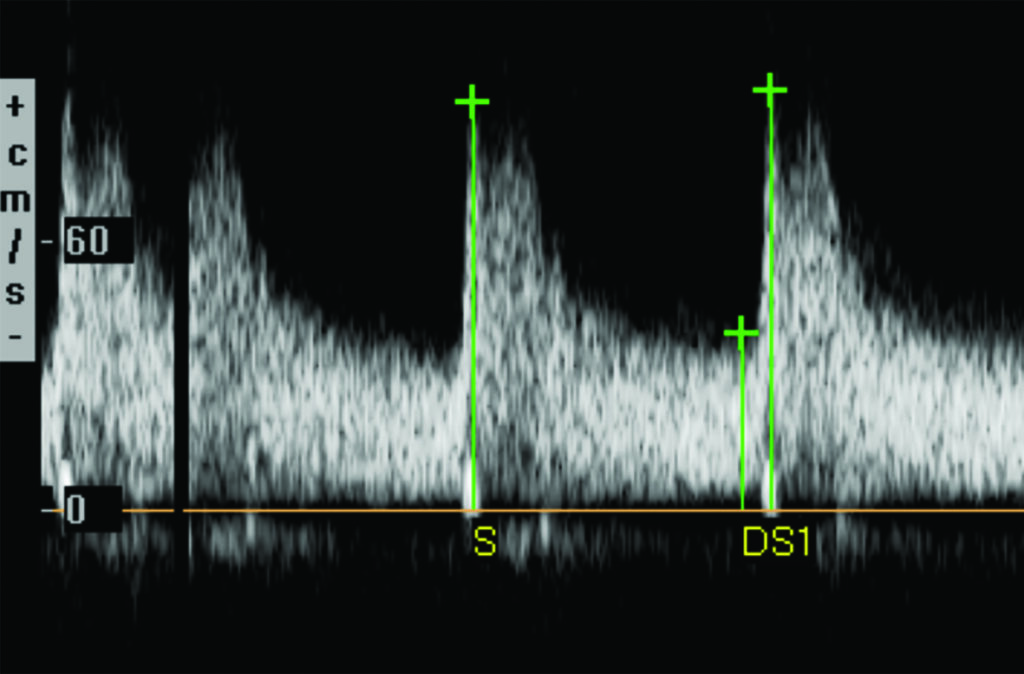

A. Velocidad del pico sistólico es la determinación de la velocidad máxima del flujo sanguíneo durante la sístole. Utilizando como criterios de estenosis los descriptos en la Tabla 1. Compartimos dos casos (Fig. 5, Fig. 6), con mediciones normales y patológicas.

| Tabla 1. Criterios de estenosis según la velocidad del pico sistólico | |

| Porcentaje de estenosis | Velocidad del pico sistólico |

| 0-59% | <220 cm/s |

| 60-79% | 220-300 cm/s |

| 80-99% | >300 cm/s |

Habitualmente se puede obtener un espectro de onda para el análisis de la velocidad del pico sistólico en el 92% de los casos. En el 8% restante, la arteria renal se visualiza parcialmente.